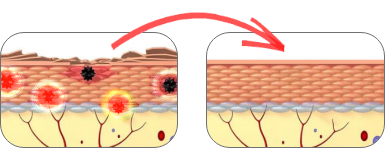

4 FAZY DZIAŁANIA niemieckiego preparatu antyłuszczycowego:

Likwidacja bólu, swędzenia i pieczenia.

Wygaszanie ognisk łuszczycy i jej przyczyn na głębokim poziomie komórkowym.

Znikają WSZYSTKIE objawy łuszczycy.

Uodpornienie organizmu na nawroty choroby.

Cały proces trwa zazwyczaj od 5 do 14 dni.